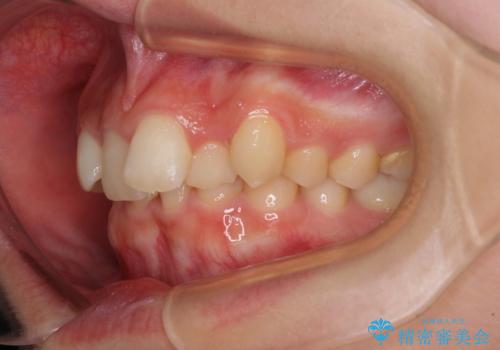

- 下顎前歯が欠損しており、前歯がデコボコとなっている歯並びを気にして来院された患者様です。

下顎の左右側切歯2本が欠損しており、上顎歯列がデコボコとなっている状態でした。

下顎歯列に対して上顎歯列が相対的に大きくなっているため、デコボコとなっているだけでなく、下顎前歯が見えなくなるくらいのディープバイトにもなっていました。